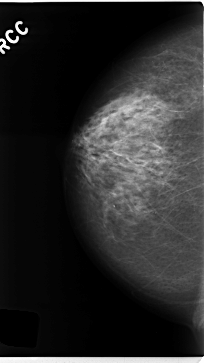

C_0228_1.RIGHT_MLO

C_0228_1.RIGHT_CC

RIGHT_CC LINES 4712 PIXELS_PER_LINE 2648 BITS_PER_PIXEL 12 RESOLUTION 50 NON_OVERLAY

RIGHT_MLO LINES 4704 PIXELS_PER_LINE 2672 BITS_PER_PIXEL 12 RESOLUTION 50 NON_OVERLAY